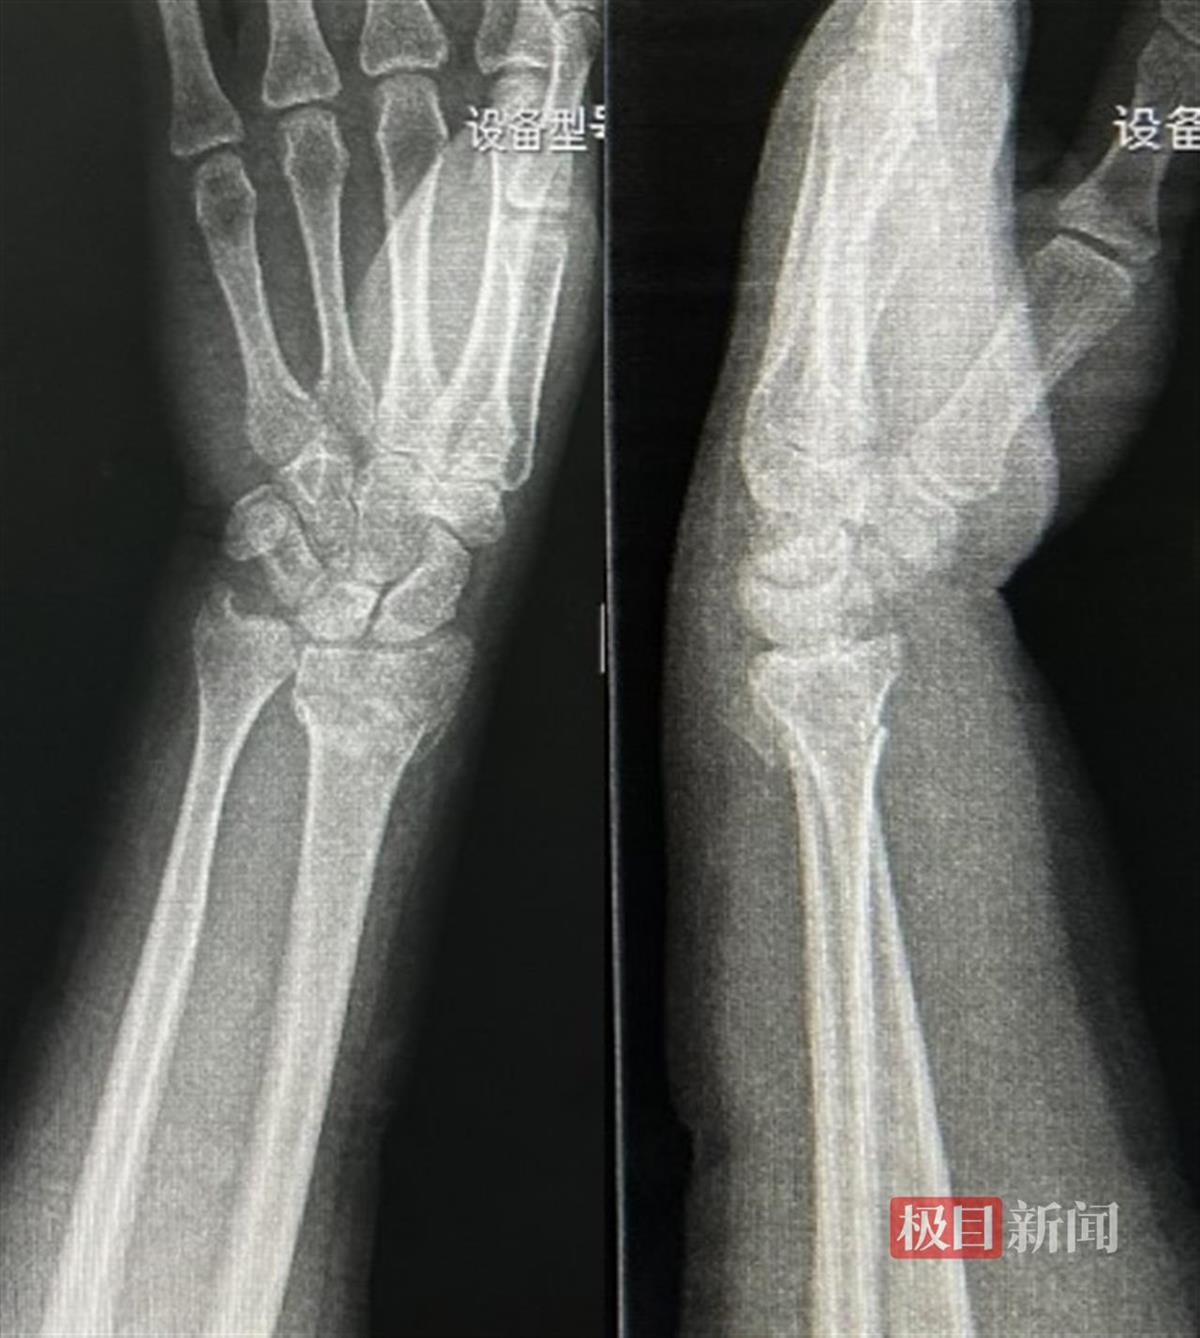

今年1月下旬,冯先生爬梯子安装灯笼时意外摔伤,就近就诊检查结果是腕部桡骨远端骨折和骨折断端明显移位。辗转两家医院,医生都建议冯先生住院手术。“可是三天后就是我儿子的婚礼,婚礼在老家河南举行,如果住院手术,铁定就赶不上婚礼了。”冯先生说,自己经朋友介绍,找到了湖北省中医院急诊科。

冯先生的伤后腕关节正侧位片

“患者来的时候,手腕红肿且严重变形,疼得满头大汗,再三请求我们不要给他做手术,因为他想赶回河南老家参加儿子的婚礼。”接诊的宋小龙医生回忆道。当时,宋小龙医生查看了X线检查结果,考虑到冯先生的请求,与急诊科外科主任马毅讨论后决定实施中医正骨手法。在马毅主任的指导下,宋小龙和李博宁两位医师配合施行了手法复位+腕部固定的中医特色治疗方案。拔伸牵引、折顶屈曲、捏挤尺偏,所有治疗一气呵成,随后以医院自制消淤膏外敷,配合支具予以固定。复位后,冯先生说:“虽然复位的时候有些痛,但复完位就马上不痛了,手腕形状也正常了。”复查X线,骨折端对位对线良好,掌倾及尺偏完全恢复。治疗后,宋小龙向冯先生叮嘱了复位后固定的注意事项,并交代了复查的时间。当日,冯先生在家人的陪同下回到了老家河南,并如期参加了儿子的婚礼。